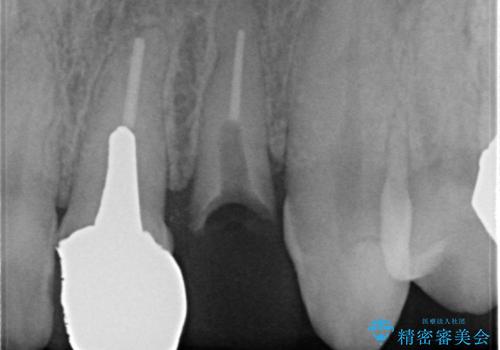

X線撮影や歯周組織検査から、クラウン下の虫歯の再発や歯の破折が疑われる状況でした。

左上2は、クラウン メタルコアの除去を行ったところ虫歯の再発や亀裂を認め、長期的な予後の期待が難しいことから抜歯を行い

ブリッジで審美性の回復を行っていく運びとなりました。